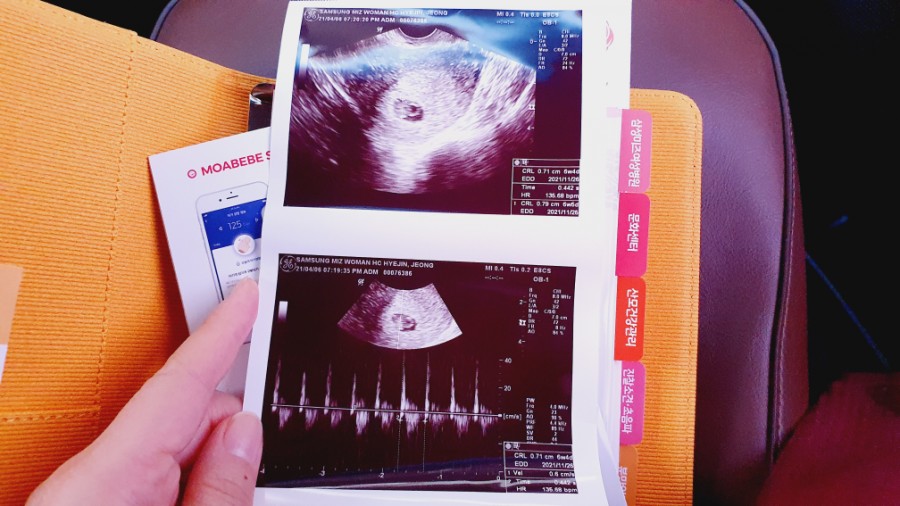

임신 6주 차 아기의 심장 소리를 듣고 신기하고 가슴이 뜨거워졌다.신기하다 심장 소리를 흘려도 아직 내 안에 아기가 있다는 게 실감이 안 나나중에 얘가 동그랗게 될 거라고 생각하니 그것도 신기하네.

심장 소리를 듣고 산전 검사를 했다

심장소리를 듣고 모자수첩을 받았다